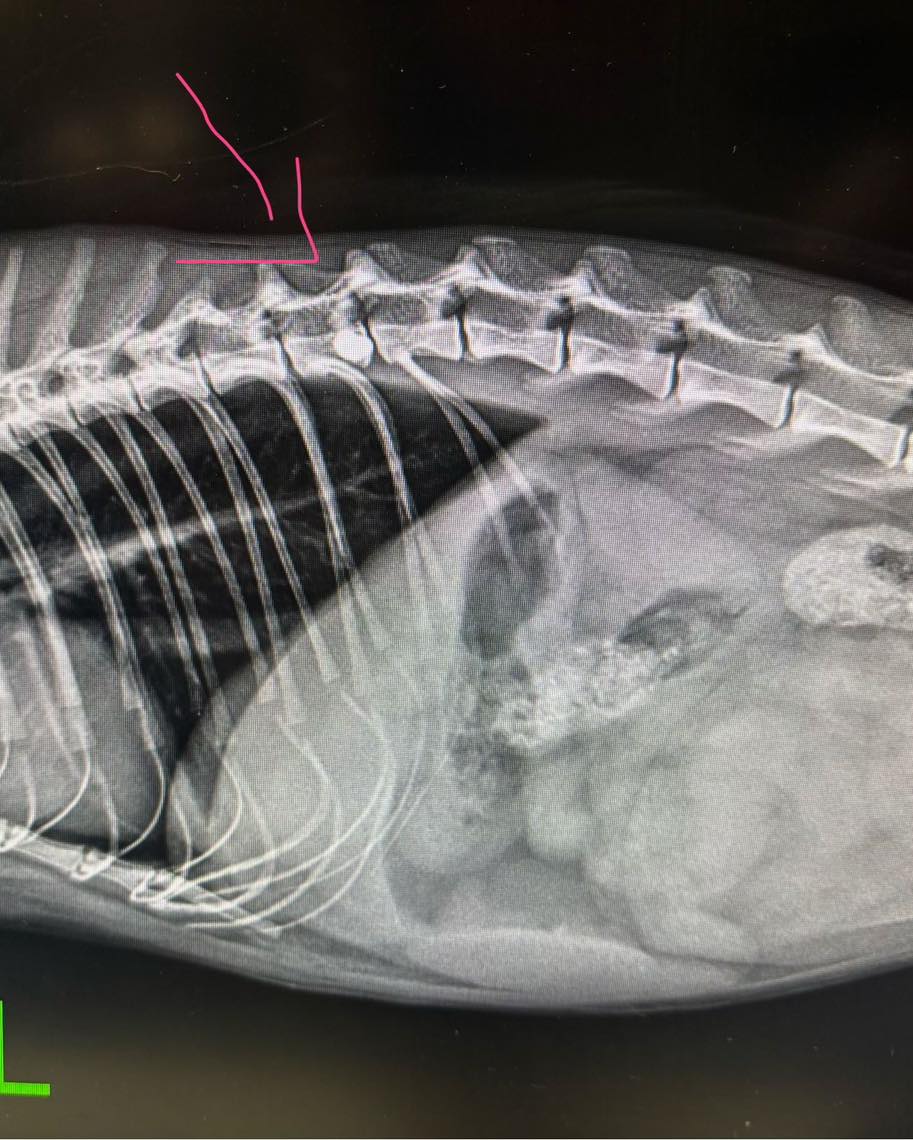

Jak przekazano, młody kocurek został postrzelony z wiatrówki w kręgosłup. Skutki były bardzo poważne. Doszło do paraliżu tylnych kończyn oraz zaburzeń w oddawaniu moczu i kału. Pocisk, bo takie imię mu nadano, trafił pod opiekę specjalistów. Zabieg został opłacony dzięki darczyńcom, którzy wsparli Gostyńskie Stowarzyszenie Przyjaciół Zwierząt "Noe". Dziś kot wciąż jest leczony i rehabilitowany, ale jego stan wyraźnie się poprawia.

- Nie pisaliśmy na razie nic, bo rokowania były takie niepewne. Czy przeżyje, czy nie przeżyje, czy nie będzie sparaliżowany. To była poważna rana w kręgosłupie. Teraz jest już po operacji, odzyskuje władzę w tych tylnych łapkach i całkiem nieźle sobie radzi. Myślę, że z tego wyjdzie - mówi Aleksandra Gerowska.

Schronisko zapowiada, że sprawa zostanie zgłoszona na policję. Osoby, które mają jakiekolwiek informacje na temat osoby strzelającej do zwierząt w Ostrowie koło Gostynia, proszone są o kontakt. Jak zaznaczają opiekunowie zwierząt, takie przypadki nie mogą pozostawać bez reakcji. Co szczególnie niepokojące, jak przyznaje Aleksandra Gerowska, postrzelone zwierzęta trafiają do schroniska i lecznic stosunkowo często. Chodzi nie tylko o koty, ale także psy i ptaki. Zdarza się, że śrut zostaje wykryty dopiero przypadkiem, podczas prześwietleń wykonywanych z innych powodów.

- Często żyją z tym śrutem i dopiero przy rentgenie okazuje się, że taki zwierzak był kiedyś postrzelony. To dosyć częste zjawisko tutaj w okolicy - mówi.